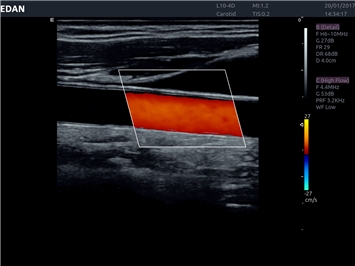

• Сосудистой диагностики

Цветовой допплер:

Да